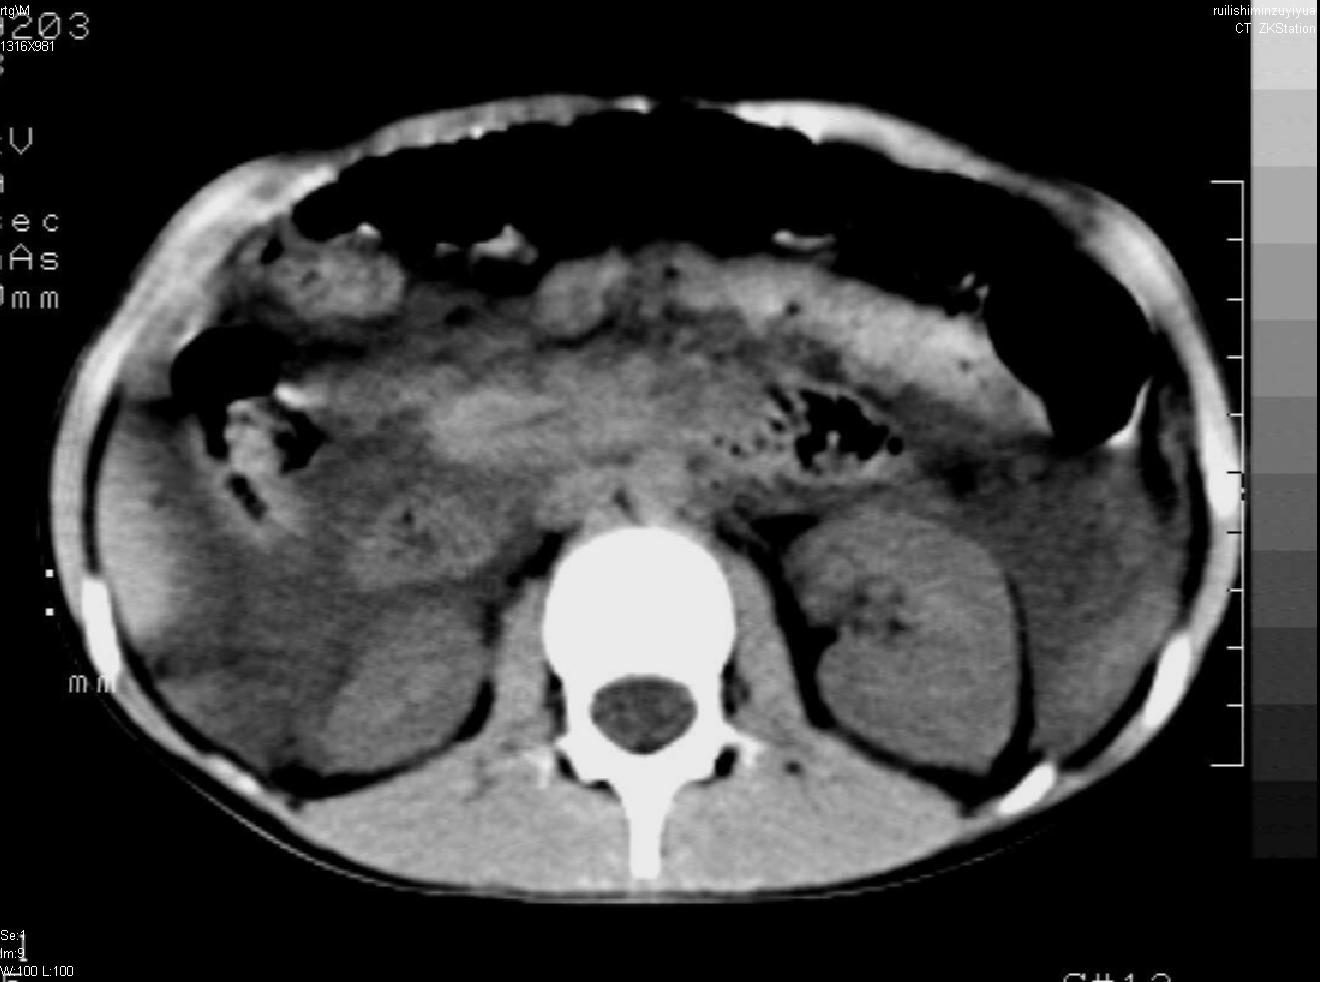

标题: PED0282:女,10岁,上腹疼痛2周 [打印本页]

标题: PED0282:女,10岁,上腹疼痛2周

b超:胆囊结石。疑坏死性胰腺炎

急性胰腺炎

支持小儿急性坏死性胰腺炎。